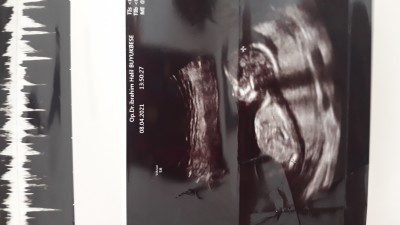

Lutfen guzel anneleer banada bi tahminde bulunun ya

doktor erkeğe benzetti sizce nedir

Evt bende erkege benzettim canim

Bencede erkek canım

Bacak arası dolu ikinci resimde öyle görüyorum canim Rabbım gönlüne göre versin

Kiz orası poposu :)

Nasil popo kız o pipi gibi ince uzun:D

Sırtı dönük kız iyi bak ensesi görünüyor :D

He kız.o zaman.benim gördüğüm kordon:D olsun üstteki resme baktım şimdi nubu yukarıda gibi erkek gibi

Ben bu postu sabah gördüm sanki, yoksa yorgunluktan hayal mi görüyorum. Bence kız

Erkege benzettim canım hakkında hayırlısı

Oğlumun ultrasonuna benzettim erkek gibi geldim hayırlısı olsun

bende erkeğe benzettim hayırlı sağlıklı ahlaklı evlat olsun inşallah cnm

Erkek geldi icimde sirt ustu yatan hep erkek oluyo neyse

Bende erkeğe benzettim cnm

tipini erkege benzettim